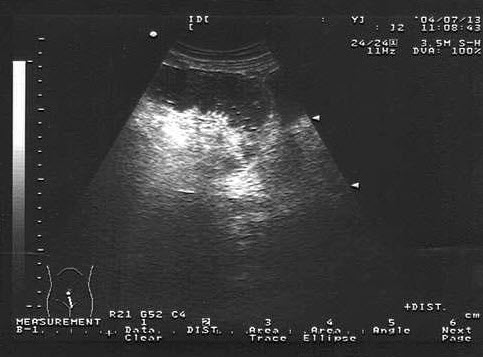

男性,右侧阴囊空虚,左侧可触及,于腹腔见一个椭圆形低回声光团,边界清晰,回声尚均匀,CDFI:血流信号丰富。如图所示,考虑为()

A.隐睾并精原细胞瘤

B.腹腔囊肿

C.腹腔淋巴结

D.畸胎瘤

E.腹腔淋巴瘤